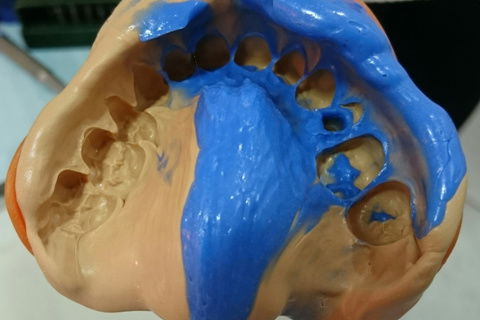

Moldagem de trabalho.

Moldagem de trabalho com transfer personalizado.